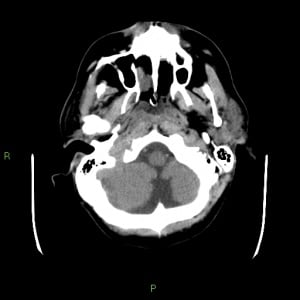

Radiographic features on CT

Typically seen as prominent retrocerebellar cerebrospinal fluid (CSF) appearing space with a normal vermis and normal cerebellar hemispheres.